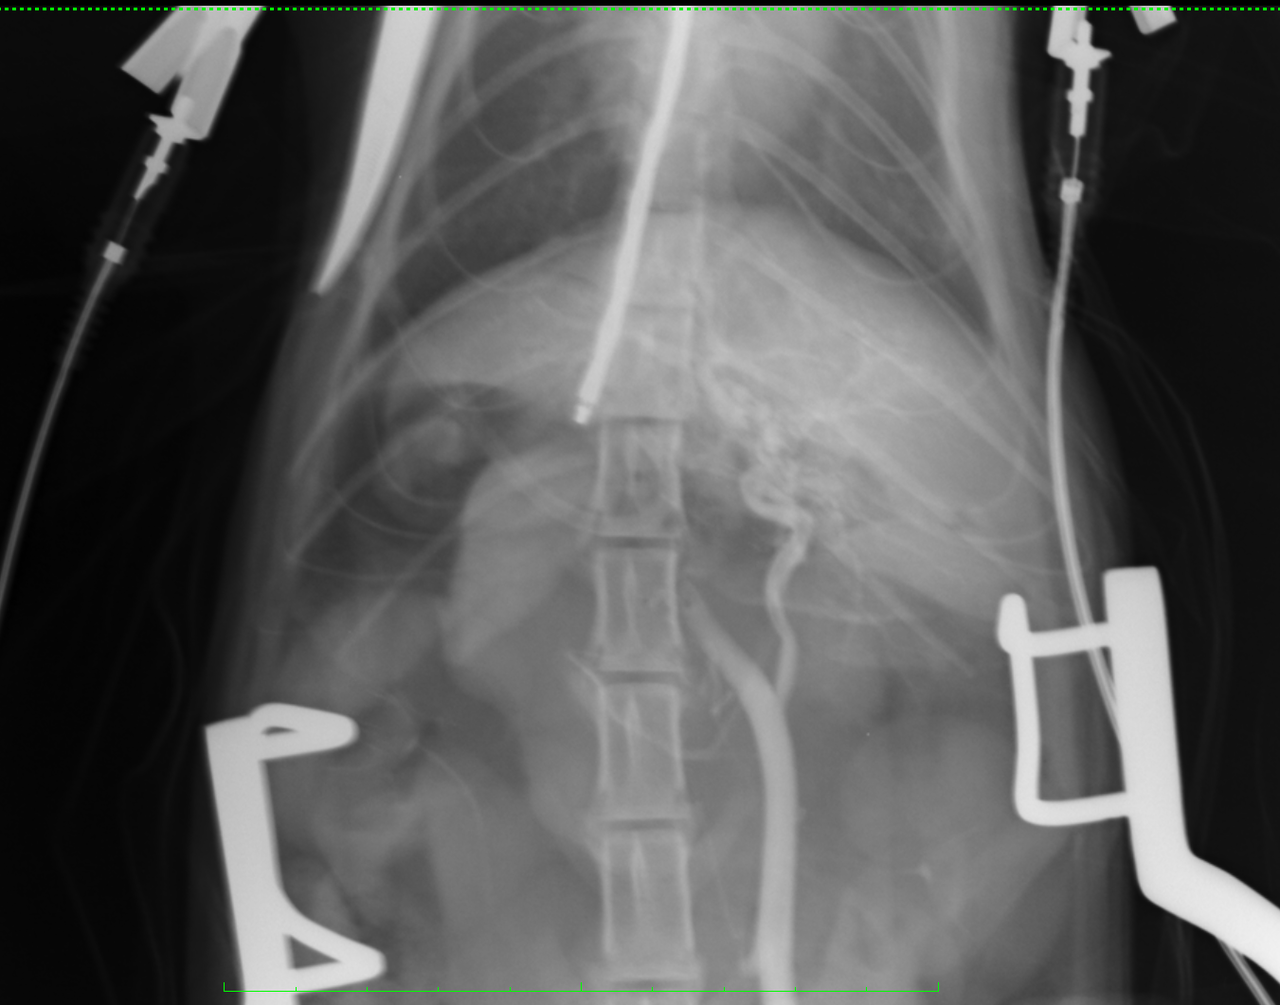

本日、猫の門脈体循環シャント(門脈シャント、PSS)の手術がありました。 前回同様に外科アドバイザーを執刀医に迎えての手術です。 今回ご紹介するのは手術中の門脈造影のレントゲン写真です。 無処置の画像では門脈枝はほとんど造影されていません。こちらはシャント血管を完全に絞めた状態です。 肝臓内の門脈枝の血流量が増えた事が判ります。

但しこの時の門脈圧は25cmH2Oでした。 処置前の門脈圧は8cmH2Oでしたので圧が高くなりすぎています。 シャント血管の絞め方を少し緩め、レントゲン検査です。 この状態でも完全結紮と同様に十分な門脈血流が観察できます。

この状態での全身の血流、血圧を安定させるため 少し時間をおいて門脈圧の測定です。 17cmH2O 結紮時の許容門脈圧は 結紮前の値を10cmH2O以上超えないことですので この状態での部分結紮で閉腹します。